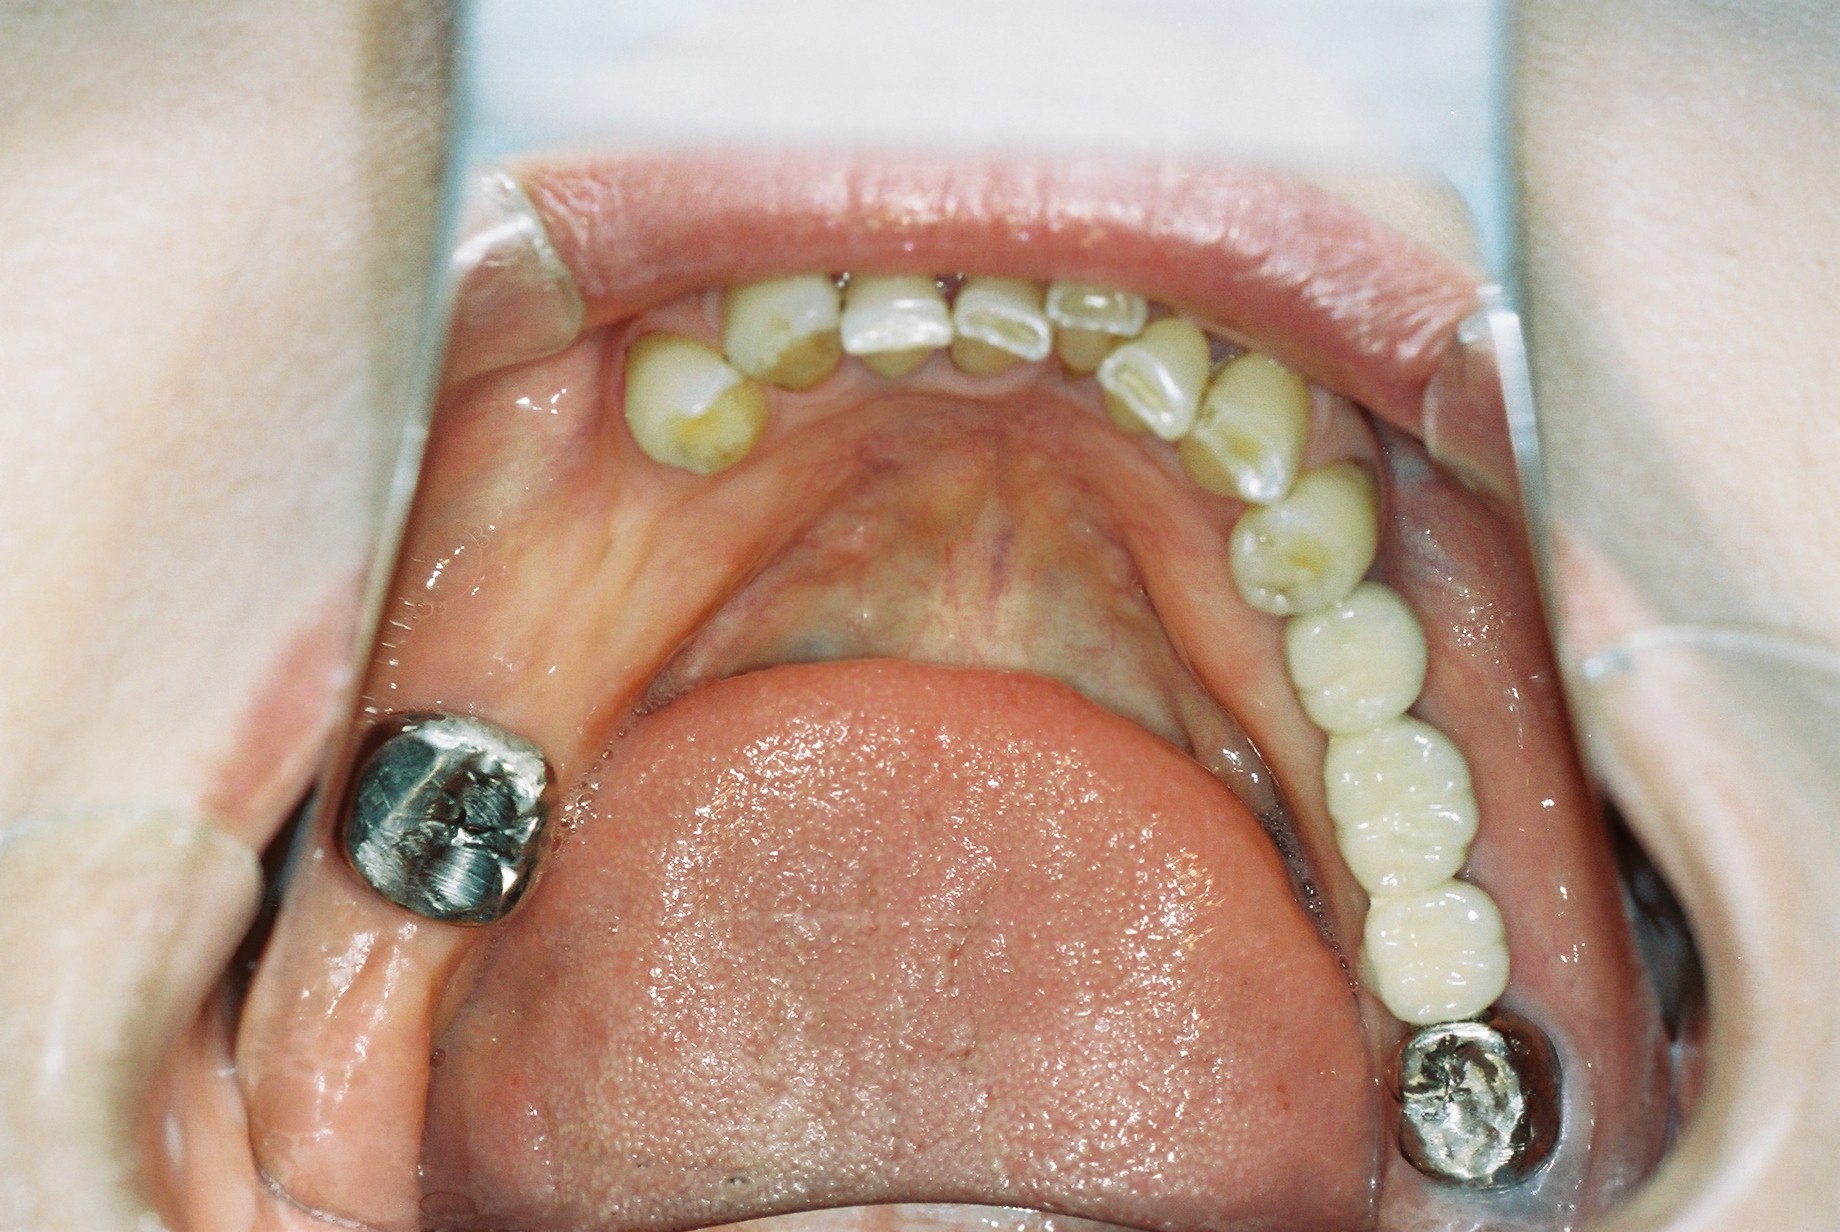

こちらはそれぞれの残存歯の後方部が両方ともないためKennedyⅠ級となります。

こちらも正中をまたいでいますが残存歯の後方部が両方ともないのでKennedy I級です。